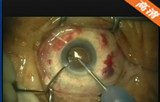

白内障超声乳化吸除联合爱尔康 ReSTOR+3多焦人工晶体植入术

该手术在10点钟位透明角膜主切口制作,前房注入粘弹剂,2点钟位侧切口制作,撕囊镊做连续环形撕囊,做水分离和水分层 ,预吸晶状体皮质 ,超乳劈核法劈核,并逐块乳化吸除核块以及皮质,I/A吸除残留的皮质并对后囊膜进行抛光,前房及囊袋注入粘弹剂,植入爱尔康多焦人工晶状体,吸除前房以及人工晶状体后的粘弹剂。